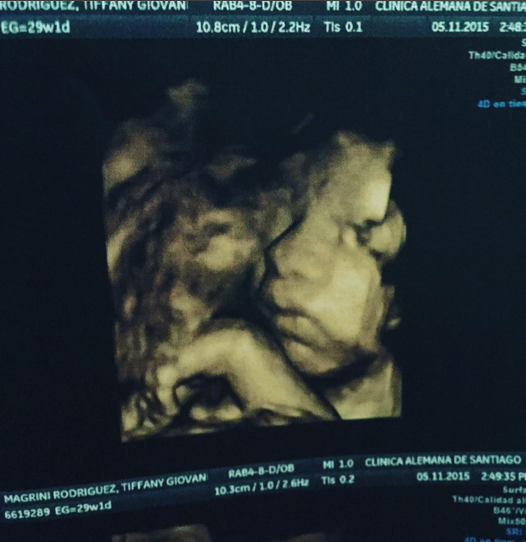

En tanto, el bailarín subió una foto de la última ecografía de su hijo Gianfranco, quien está a un mes de nacer.

“Mi futuro mejor amigo!!! #GianFrancoCabreraMagrini hoy en su ecografia resultó que esta creciendo sano y fuerte gracias a #Dios”, escribió el ex Rojo.